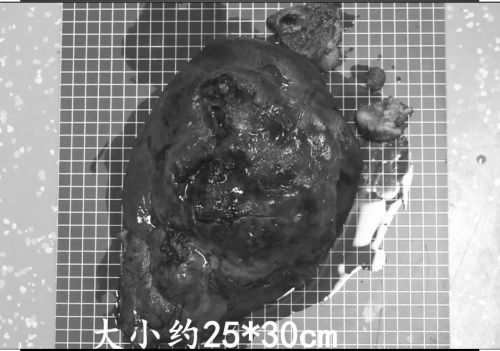

切下的左肝体积是正常的六倍。

6月26日,杨尽晖主任医师带领高泰龙医师等,在全麻下为患者施行开腹胆囊切除、胆道探查、左肝外叶及部分左肝内叶切除、胆道T管引流手术。术中发现,左肝的数十个脓肿中最大的一个已经破裂,抽出脓液1000毫升,切下的病肝重达1732g。医生还从胆管内取出一个1.5×1.2×13cm大小的结石,解除了造成胆总管梗阻的原因。在切除胆囊的过程中发现,胆囊被十二指肠和横结肠包裹,于是小心翼翼地将肠子和胆囊分离,成功切除胆囊,顺利完成手术。